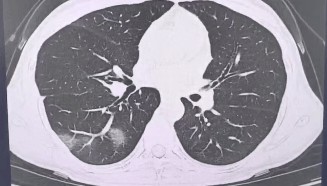

查出流感没在意,女子硬扛三天后肺都“白”了……

流感不过是一场“重感冒” 吃点药休息休息就能好? 浙江杭州39岁的程女士(化姓)是名“工作狂”, 经...